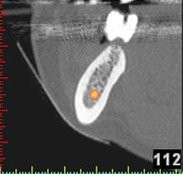

(siehe Bild 3 und 4).

Mit diesen gewonnenen Informationen und Planungen stellt der Zahnarzt interaktiv spezielle Bohrschablonen her. Diese ermöglichen eine exakte Positionierung der Implantate, so wie vorher am Computer geplant.